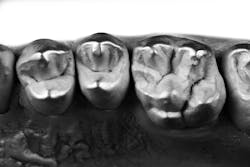

I always taught my students to pause and enjoy looking at beautiful natural teeth whenever possible.1 Many patients present with intact teeth worthy of observation and documentation. In that regard, having a library of pictures and stone models is a must. As of today, I strongly suggest analogue PVS impressions because digital scans and printers are not able to reproduce the microtexture of natural teeth (figure 1).

Complete records also imply using a top-quality photography equipment (mirrorless interchangeable lens camera (MILC) system, not smartphone or point-and-shoot) with appropriate selections of light-reflecting accessories depending whether you are photographing anterior or posterior teeth (figure 2). I call my camera my third eye because it allows me to see things that are not visible with to the naked eye.